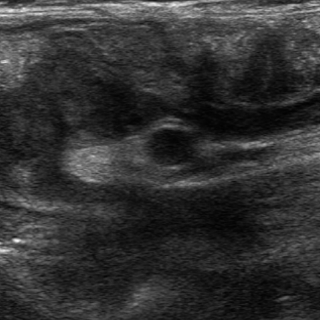

| Meme cas en coupe

longitudinale du boudin d'invagination . |